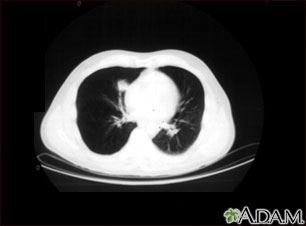

Tomografía computarizada que muestra una masa en la parte inferior derecha del tórax, cerca del corazón (lado izquierdo de la fotografía).